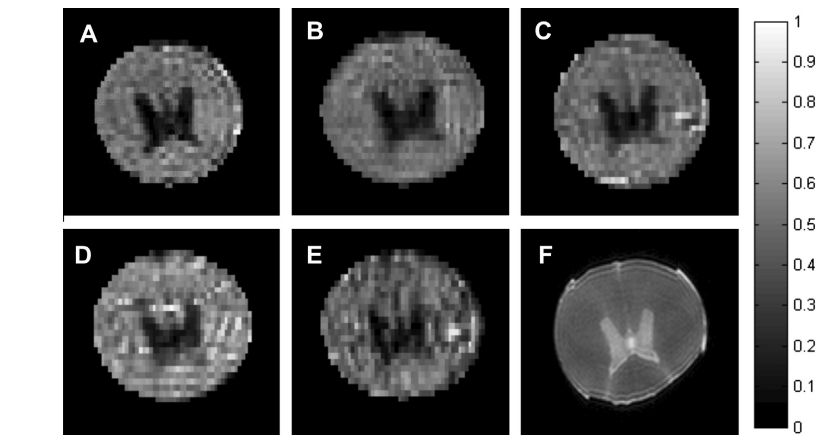

3. High-Accelerated Parallel Imaging With the Inherent Local Feature in PE-xSPEN MRI.png

Dai K, Solomon E, Lee P, Tao G, Qiu Y, Chen H, Frydman L, Zhang Z

Magnetic Resonance in Medicine, 2025